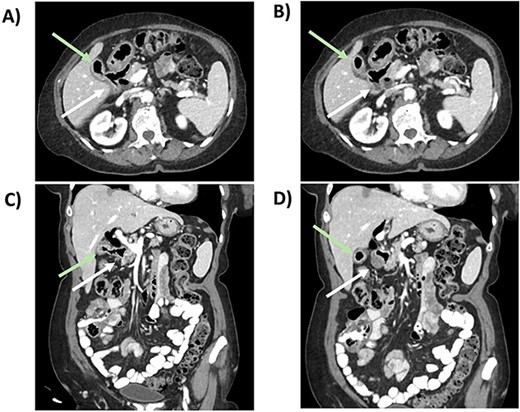

After anesthesia induction, indocyanine green 2.5 mg was administered. A Veress needle was used for entry, and four 8-mm trocars were inserted in her left mid-abdomen, two centrally and one in the right mid-abdomen (Fig. 3). An adherent small bowel loop was sharply dissected off the anterior abdominal wall. A small serosal injury was oversewn robotically with an interrupted 2-0 Vicryl suture after docking the DaVinci robot. The gallbladder was carefully separated from the adherent duodenum, and an approximately 1-cm fistula was noted (Fig. 4). The duodenotomy was repaired in two layers with an inner full thickness and an outer interrupted submucosal layer using absorbable suture (Fig. 5). Next, using FireFly to confirm biliary anatomy, the chronically inflamed gallbladder was dissected off the adherent common bile duct and right hepatic duct. After the critical view of safety was achieved, the cystic artery and duct were robotically clipped and transected. The intrahepatic gallbladder was dissected off the cystic plate, and a 10-French drain was left in the gallbladder fossa.

Trocar placement. Veress entry was performed at Palmer's point. Three additional 8-mm ports were placed approximately 6-cm equidistant as shown. The Veress entry site is increased in size to accommodate the #4 8-mm trocar. Instrumentation is as follows: 1) fenestrated bipolar 2) robotic camera 3) interchangeable port (monopolar scissor, robotic suction, prograsp) 4) tip-up with 4x4 inserted to elevate the liver 5) 5 mm assist port if needed.